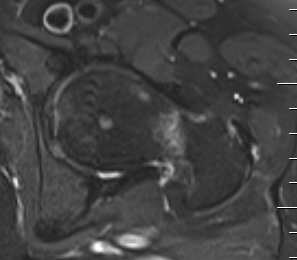

MRI

Edema / fracture line / hip effusion

MRI demonstrating edema likely across entire neck

MRI demonstrates complete fracture